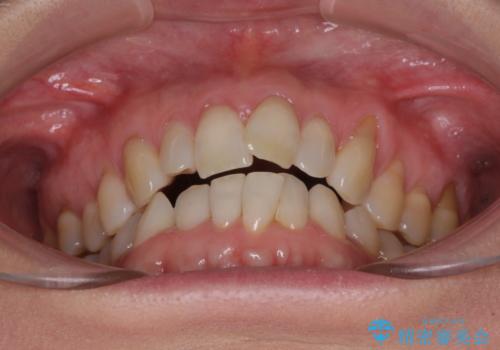

前歯のスペースが気になる インビザラインによる矯正治療

- 前歯の上下スペースによる食べにくさを気にして来院された患者様です。

インビザラインにより上下の前歯の隙間を閉じていくこととしました。